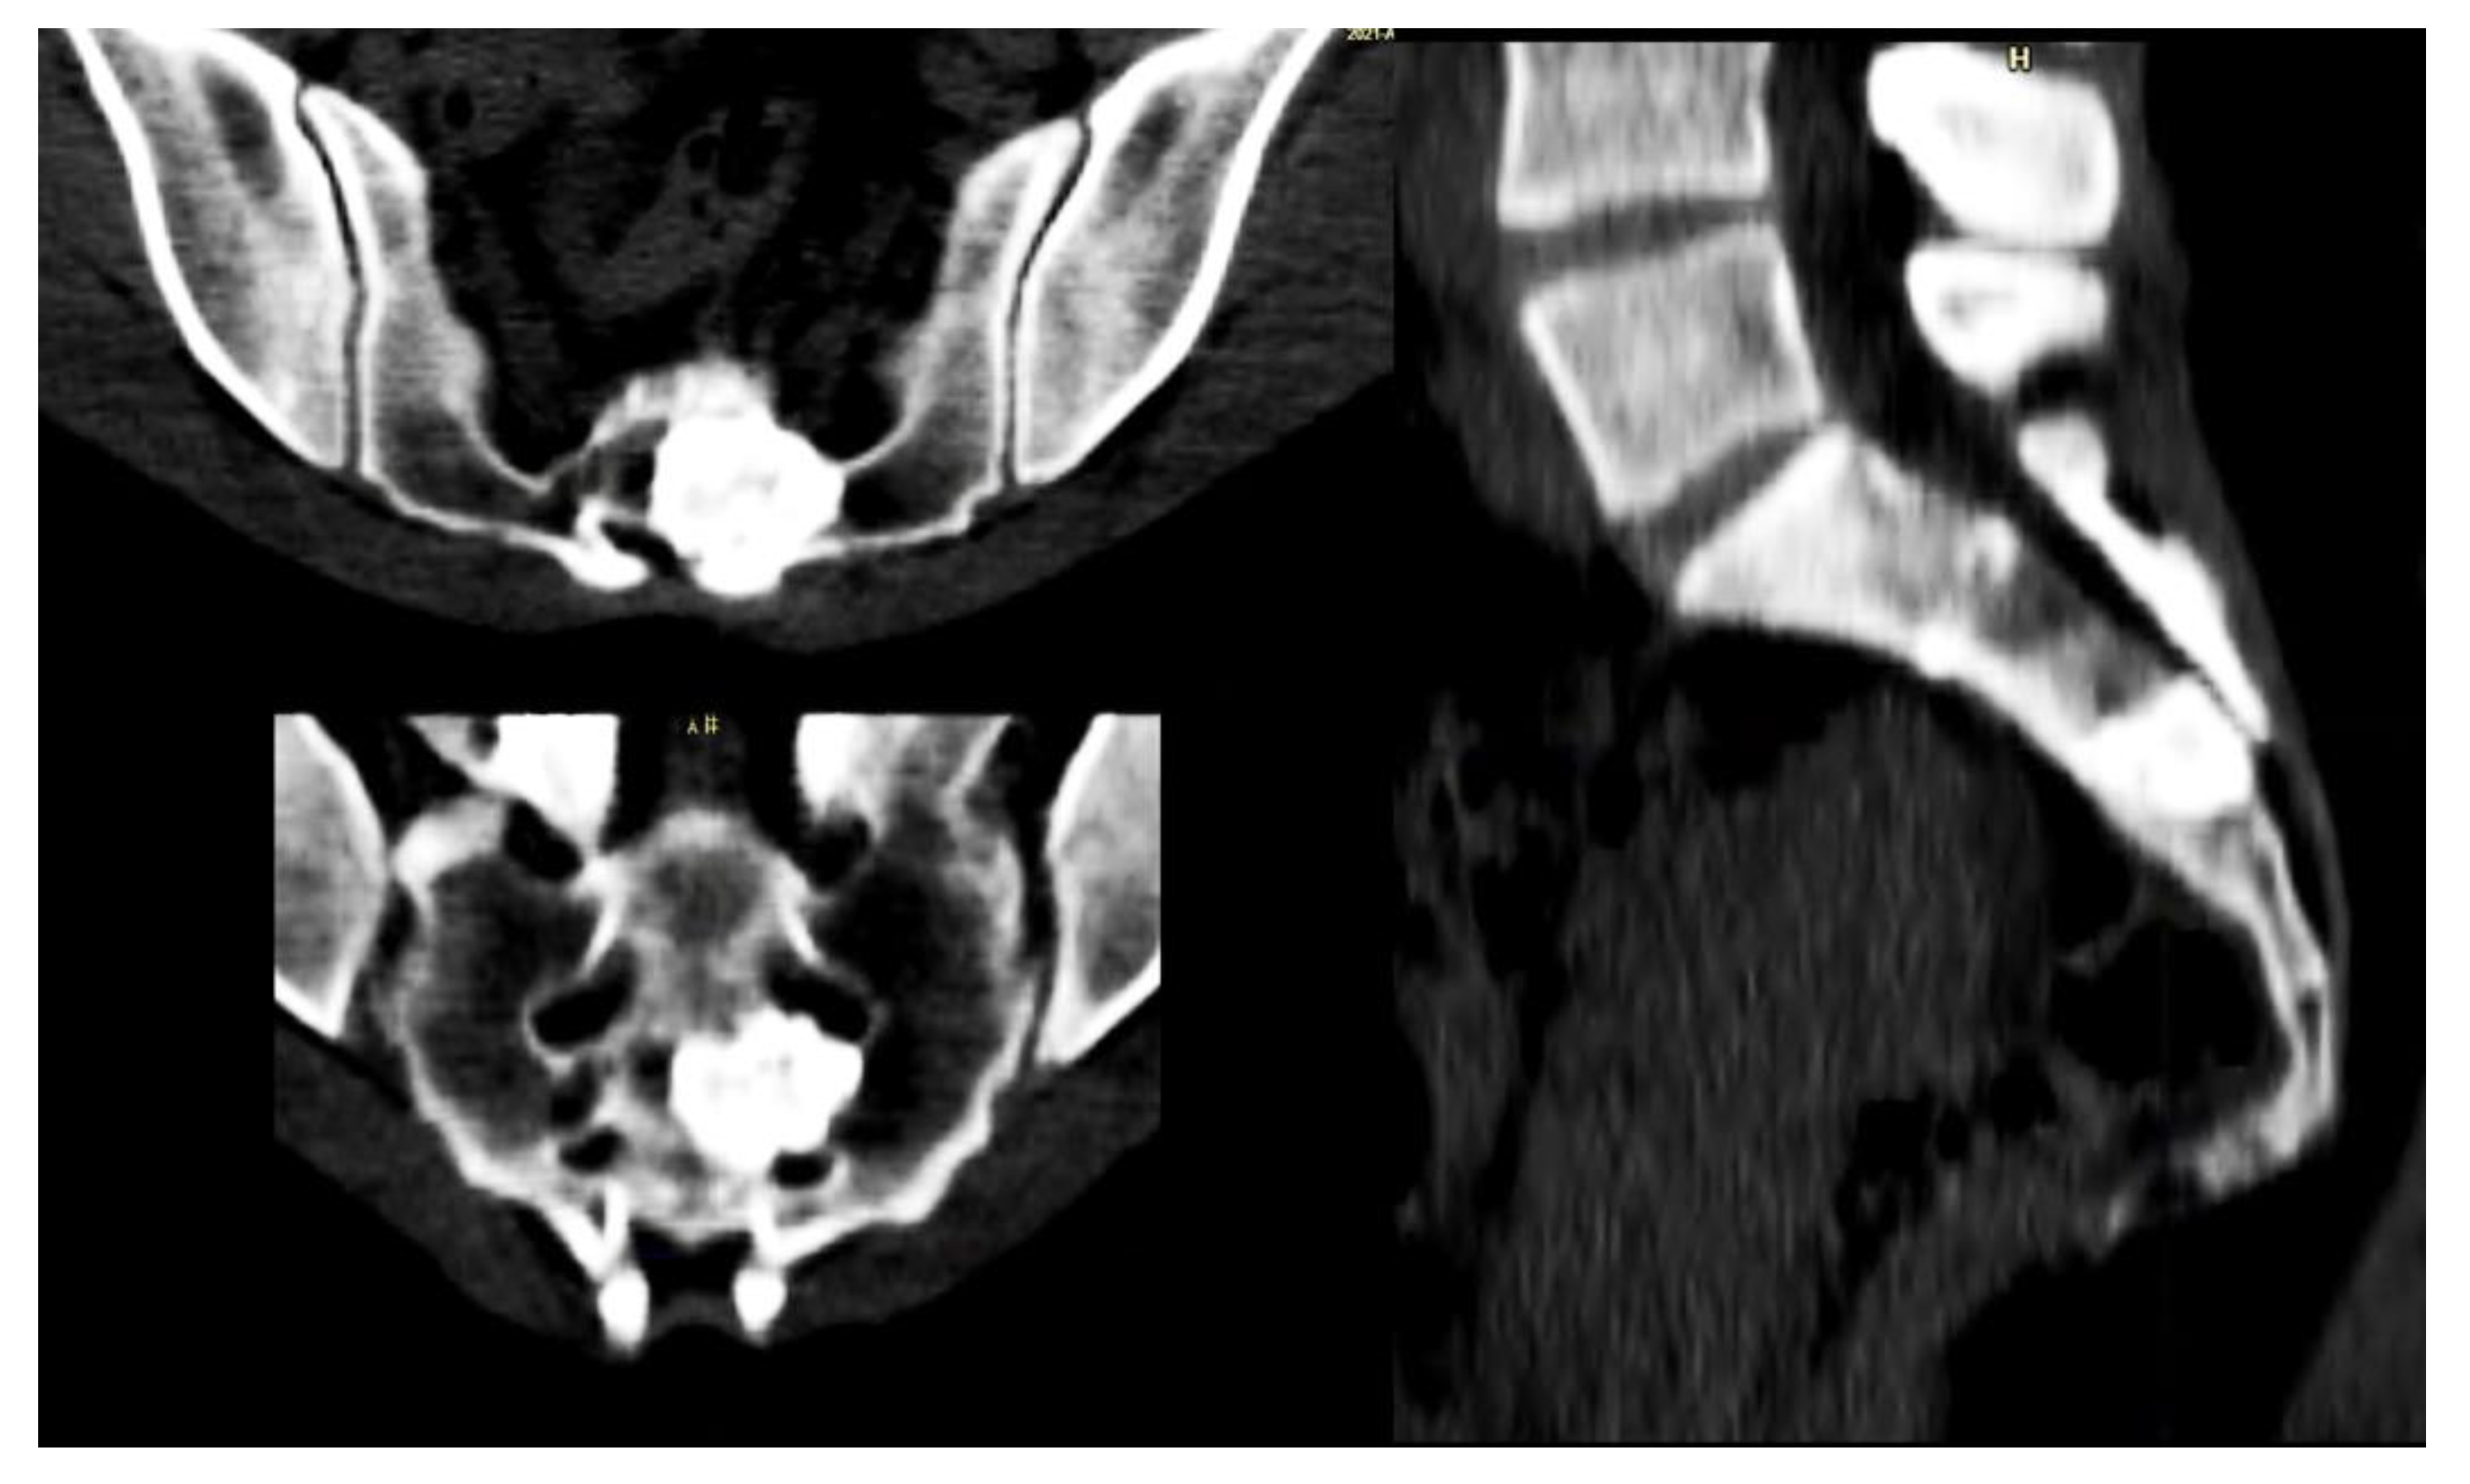

Particular attention has to be reserved for lesions located in the sacrum, where the recurrence rate is higher than in other areas, possibly due to the complex anatomy and the presence of the sacral roots (Figure 3) [22].

Figure 3. Forty-seven-year-old female patient affected by OBL of S3.